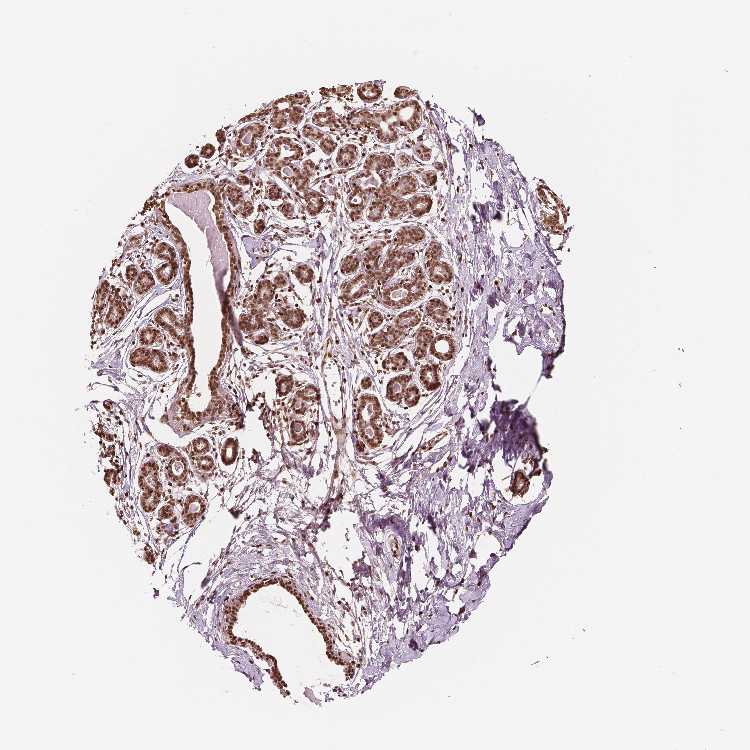

BREAST - Antibody stainingi

Antibody staining in the annotated cell types in the current human tissue is reported as not detected, low, medium, or high, based on conventional immunohistochemistry profiling in selected tissues. This score is based on the combination of the staining intensity and fraction of stained cells.

Each image is clickable and will lead to virtual microscopy that enables deeper exploration of all samples and also displays staining intensity scores, fraction scores and subcellular localization as well as patient and tissue information for each sample.

Antibody HPA042570Antibody CAB070190

Adipocytes HighHigh

Glandular cells HighHigh

Myoepithelial cells HighHigh